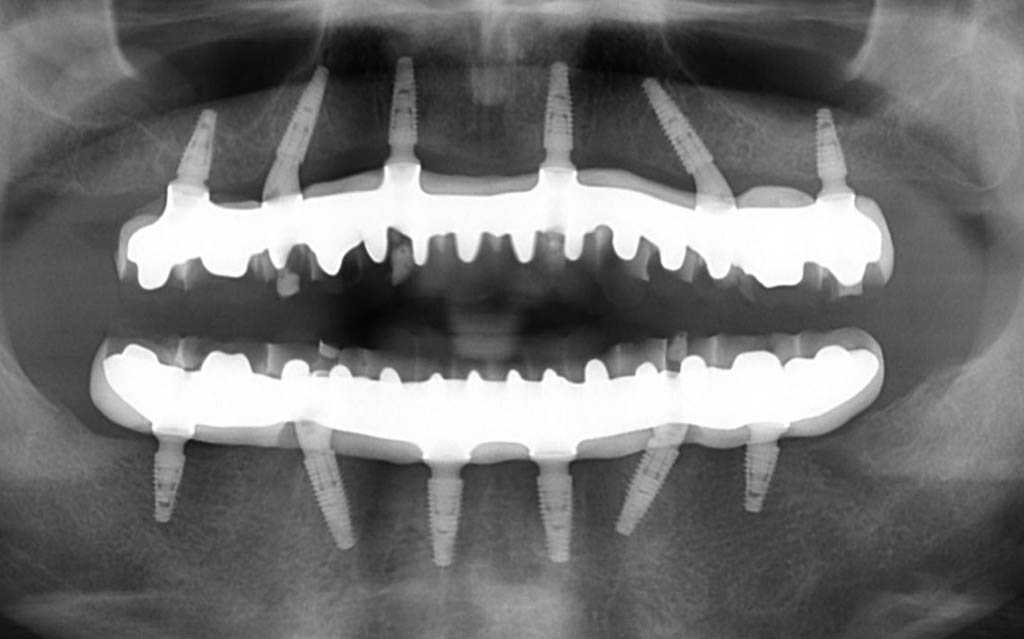

After going through the options he decided to go for a full mouth rehabilitation for the top and the bottom. We went through the process of discussing the treatment and after finalising the treatment plan. The treatment involved extractions of all the upper teeth and placement of implants on the same day. We then placed a temporary bridge on the same day, so he left the clinic on the same day with fixed teeth.

After a healing period of 12 weeks, we then started the design process of making his permanent teeth. After designing it, we did some try ins which the patient is over the moon, and now he has a fixed bridge at the top and a fixed bridge at the bottom.